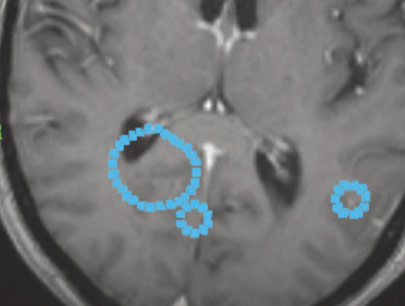

Multiple Metastasis

Radiosurgery adalah tindakan ideal untuk metastasis (anak sebar tumor ganas) ke otak.

Metastasis pada otak dilokalisir dengan baik.

SEBELUM

SESUDAH